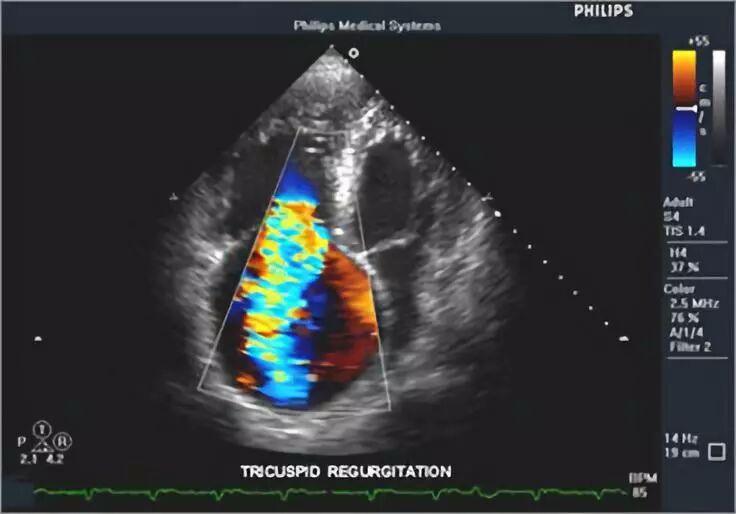

图 心脏彩超

彩色多普勒血流显像(CDFI)或彩色多普勒显像(CDI)主要是利用血液中运动的红细胞对声波的散射,产生多普勒效应,经伪彩色编码技术,在二维图像上显示彩色血流影像。不同方向的血流以不同的颜色表示。彩色多普勒超声诊断仪同时具备频谱多普勒功能,可在彩色图像上定点取样,显示多普勒频谱图,并听取多普勒信号音。